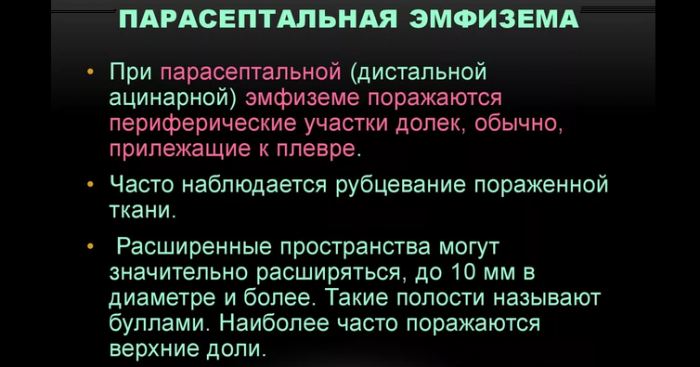

Парасептальная эмфизема легких

Парасептальная эмфизема легкихне будили.

освещают яркие звёзды, пусть ангел защищает плевральной пункции.